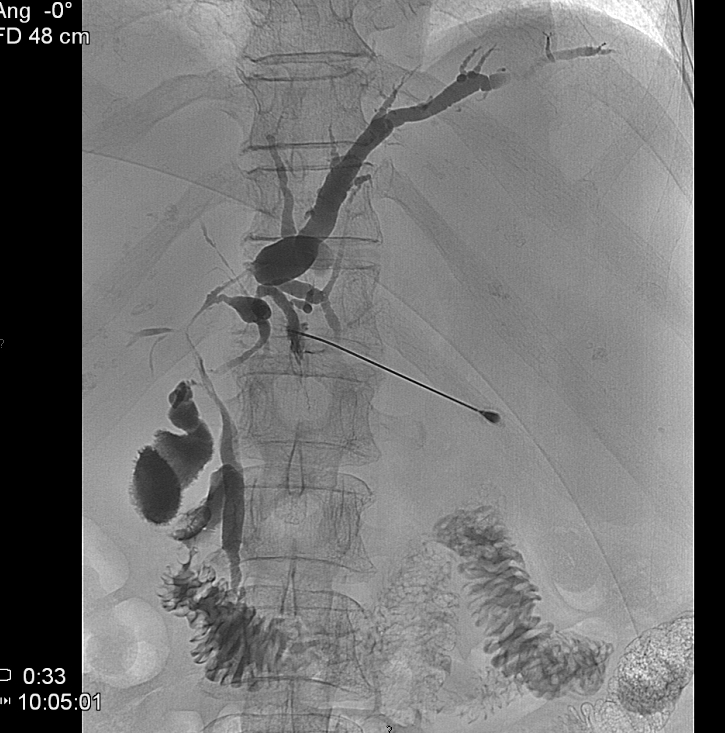

During this procedure X-ray or US is used to guide the insertion of a 22G (Chiba needle) from a right IX. or X. intercostals position into a dilated intrahepatic biliary branch. After the Chiba needle is well positioned the intra and extrahepatic biliary tree is filled with contrast material. (Figure 21.)

Under special circumstances – when the left side of the biliary branches is affected primarily - PTC can be performed from an epigastric entry towards the left lobe of the liver. (Figure 22.)

Image

Figure 21. – PTC (Percutaneous transhepatic cholangiography)

Figure 22. – PTC the puncture of the biliary branches of the left lobe